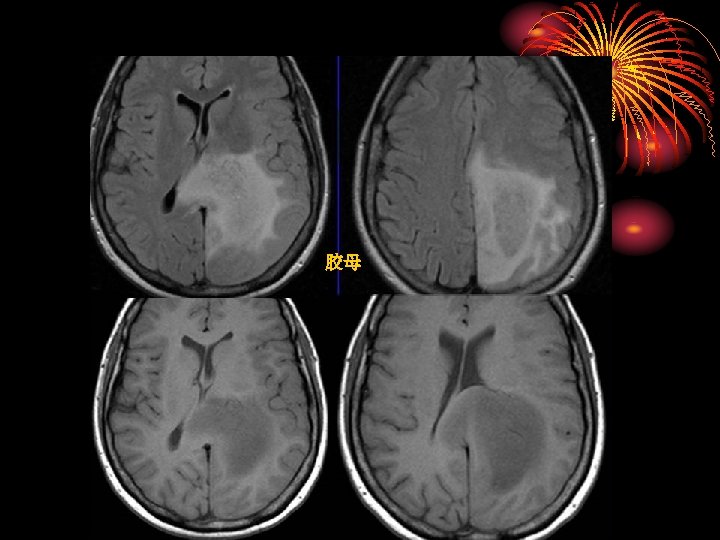

胶母 MR imaging and CT findings in 54 -year-old woman with glioblastoma. A, Axial T 2 -weighted and, B, contrast-enhanced axial T 1 -weighted MR images show a round cystic mass with complete rim enhancement and peritumoral edema in the subcortical white matter of the right frontal lobe. The signal intensity of the rim is isointense to gray matter on the T 2 -weighted image (arrow). C, Unenhanced axial CT image demonstrates isoattenuation (grade 2) of the rim (arrowhead).

胶母 Glioblastoma Multiforme: no dark line of advancing demyelination